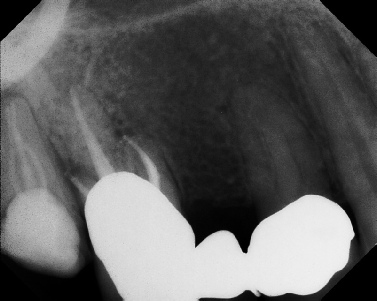

Pre-op Post-op 1 Post-op 2